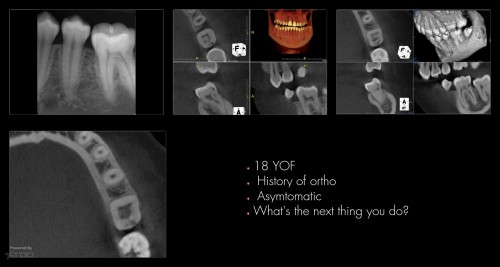

Pop Quiz

By Gary Carr / July 27, 2018